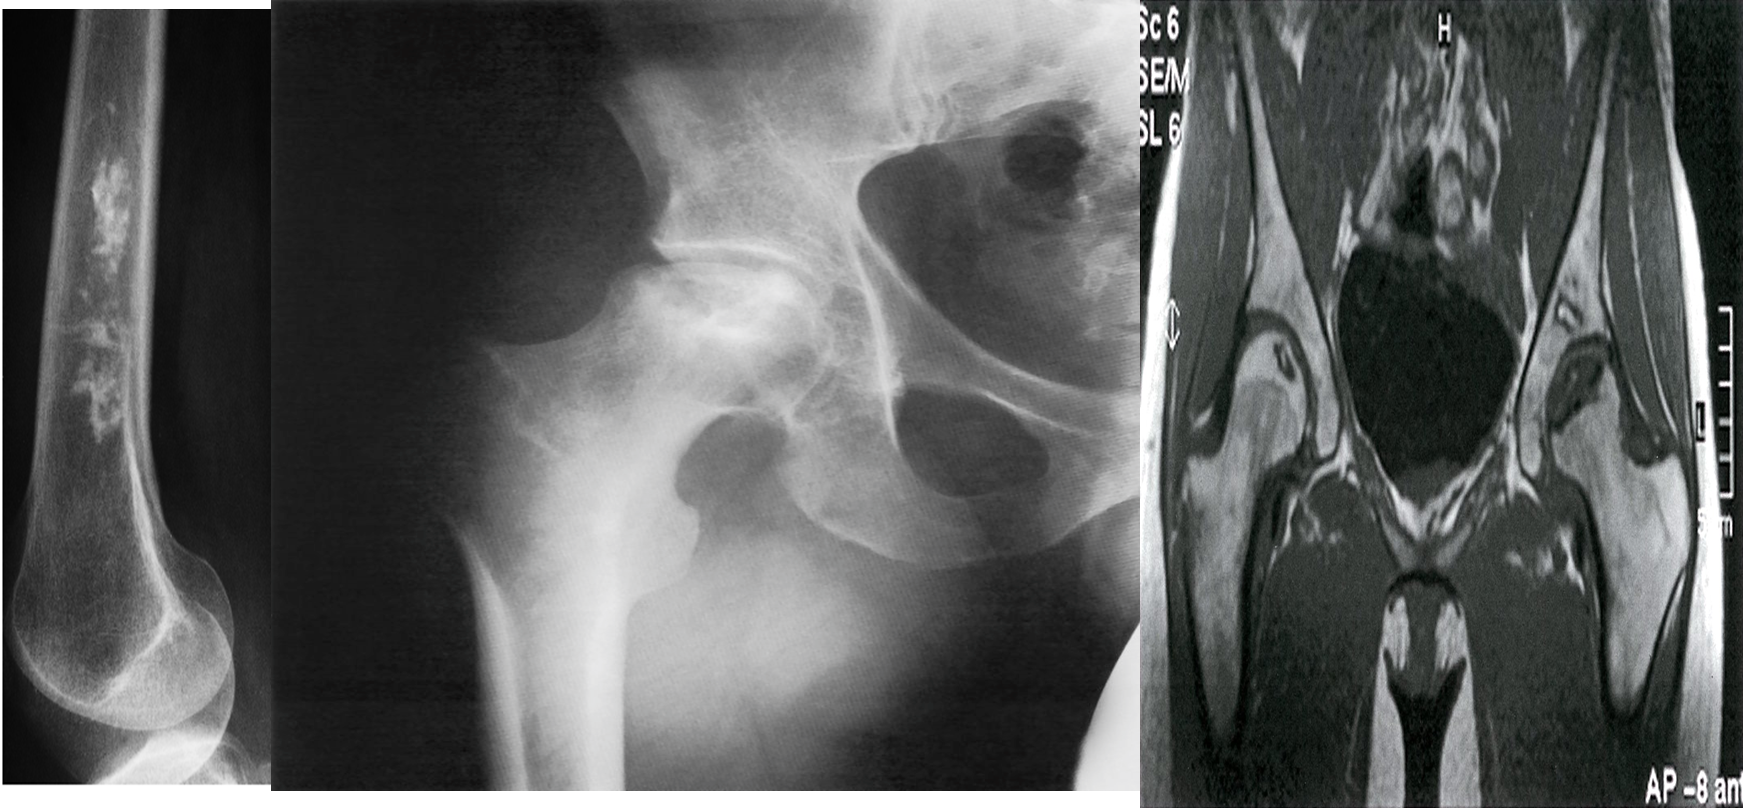

A) Bone infarct. There is calcification in the medulla of the lower end of the femur.

B) X-ray right hip (AP view) The articular surface of the femoral head is irregular (black dotted line) and the underlying bone is heterogeneous (green overlay) as a result of osteonecrosis. A zone of sclerosis (red overlay) is present along the interface with normal bone.

C) Bilateral osteonecrosis of the femoral head

MRI hips (T1 weighted; coronal view) of a 32-year-old woman with groin pain

There is a well-defined crescent-shaped area of intermediate to low signal within the subchondral marrow of the left femoral head . A thick peripheral band of even lower signal separates this region from the hyperintense normal bone marrow. On the right side, there is a slightly smaller area of abnormal oval-shaped signal within the epiphysis of the right femoral head.